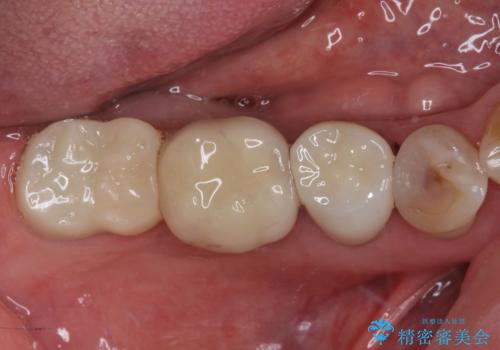

歯肉が退縮したことで見えていた歯根もセラミッククラウンで覆うことができ、清掃性も改善されました。